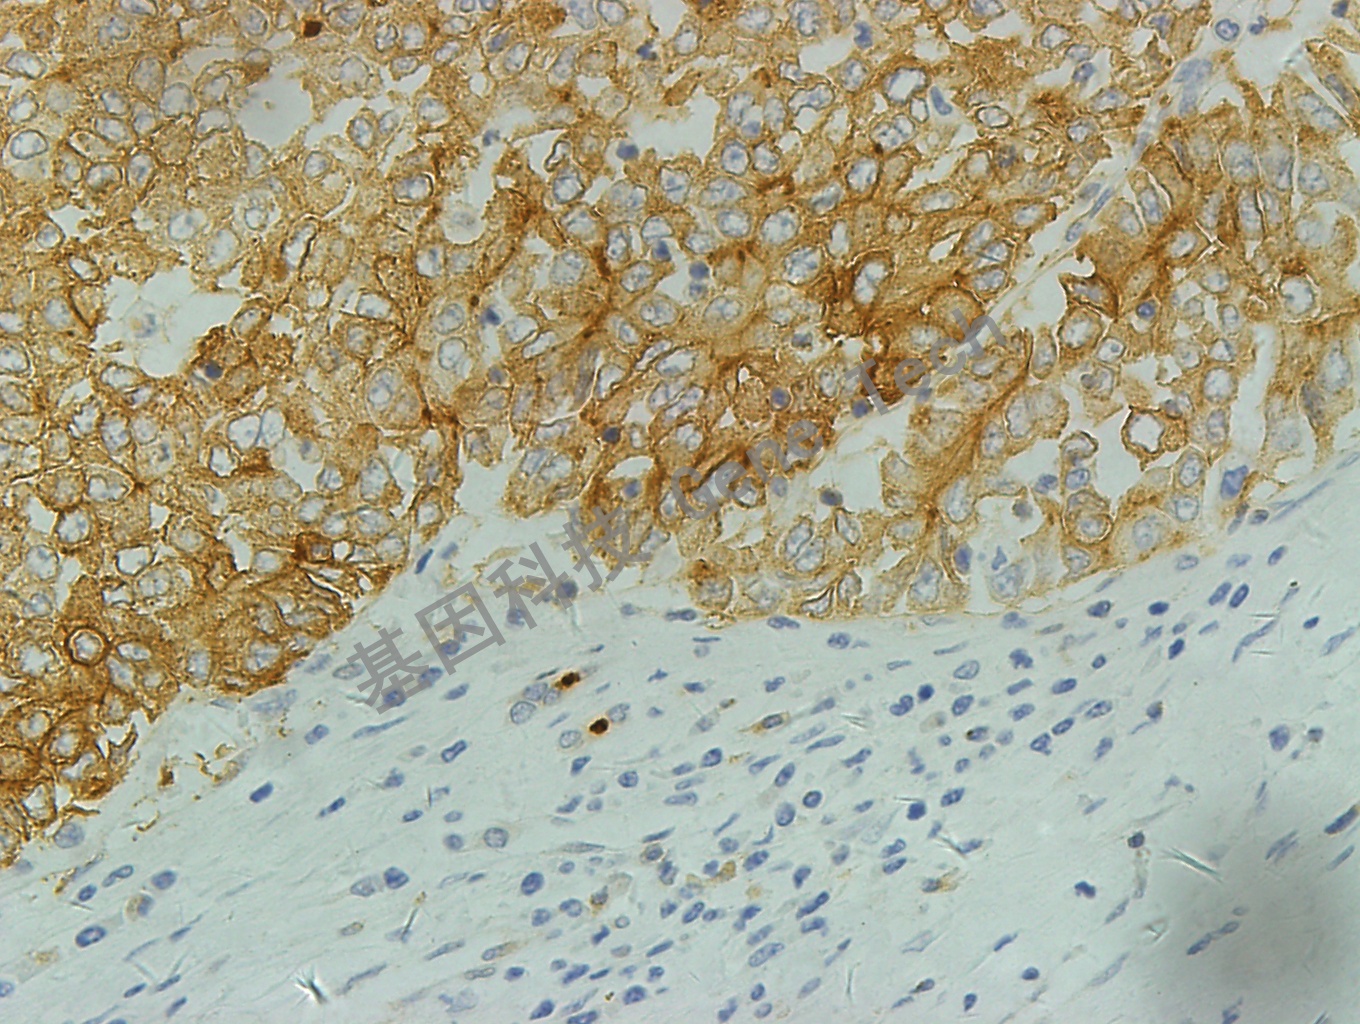

| 克隆號(hào):EP271 | 種屬:兔 | 適用染色系統(tǒng):GTvisionTM |

| 預(yù)處理:高pH熱修復(fù) | 陽(yáng)性部位:細(xì)胞膜 | 陽(yáng)性對(duì)照:肝 |

| 肝癌石蠟切片,用 P-glycoprotein(GT2223)染色,細(xì)胞膜陽(yáng)性,DAB 顯色。 | ||